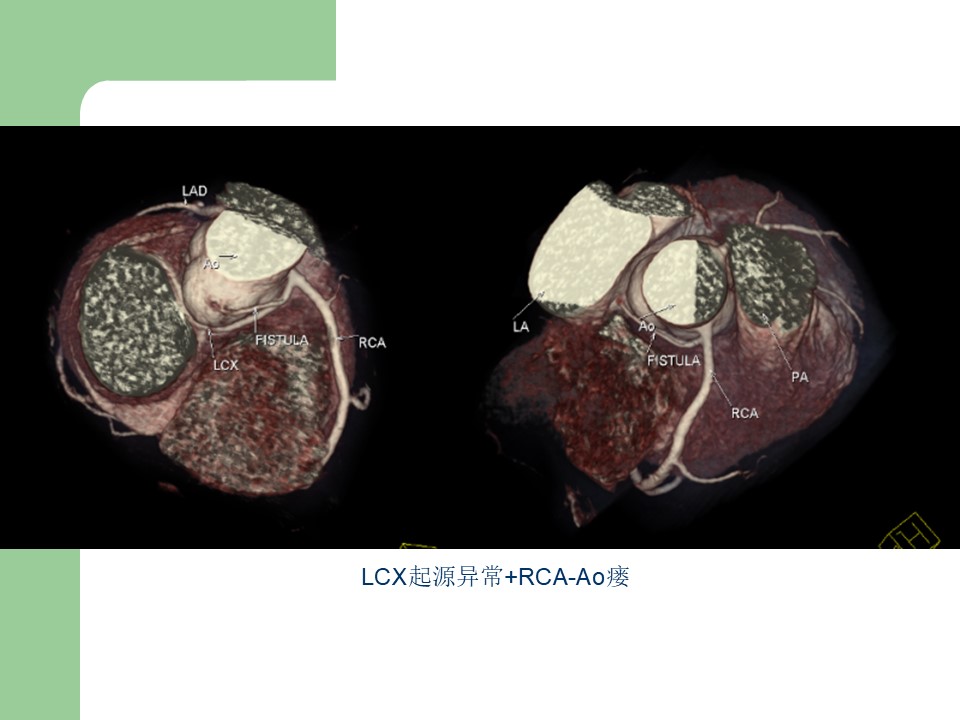

“冠状动脉常见疾病的双源CT表现” 的相关文章